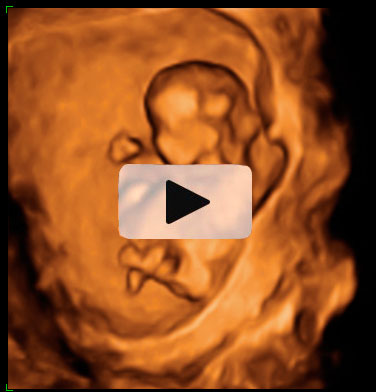

Ecografía 4D de la semana 12: Gemelos contrapeados

Ecografía en 4D de gemelos de 12 semanas "contrapeados" En este caso, el gemelo que "baila" es el que está en parte inferior de la imagen o cabeza abajo.